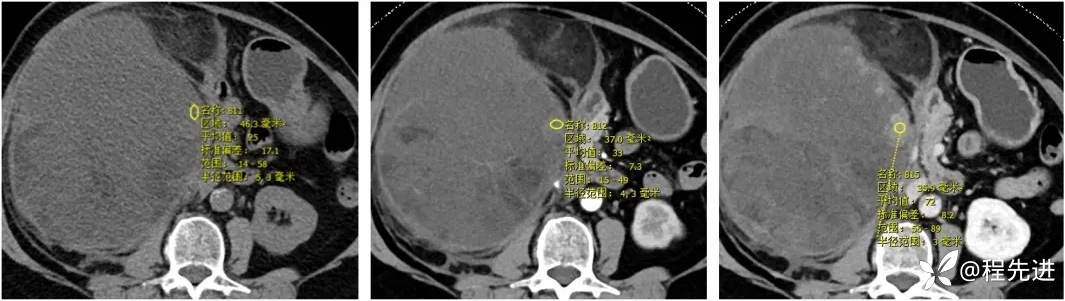

【主诉】:腹胀2月余,发现腹腔占位10天

【现病史及既往史】:患者2月余前出现腹胀,胃反酸,无寒战发热胸闷胸痛、恶心呕吐、腹痛腹泻等不适伴随症状。10天前患者自查发现腹腔占位

【检查】: